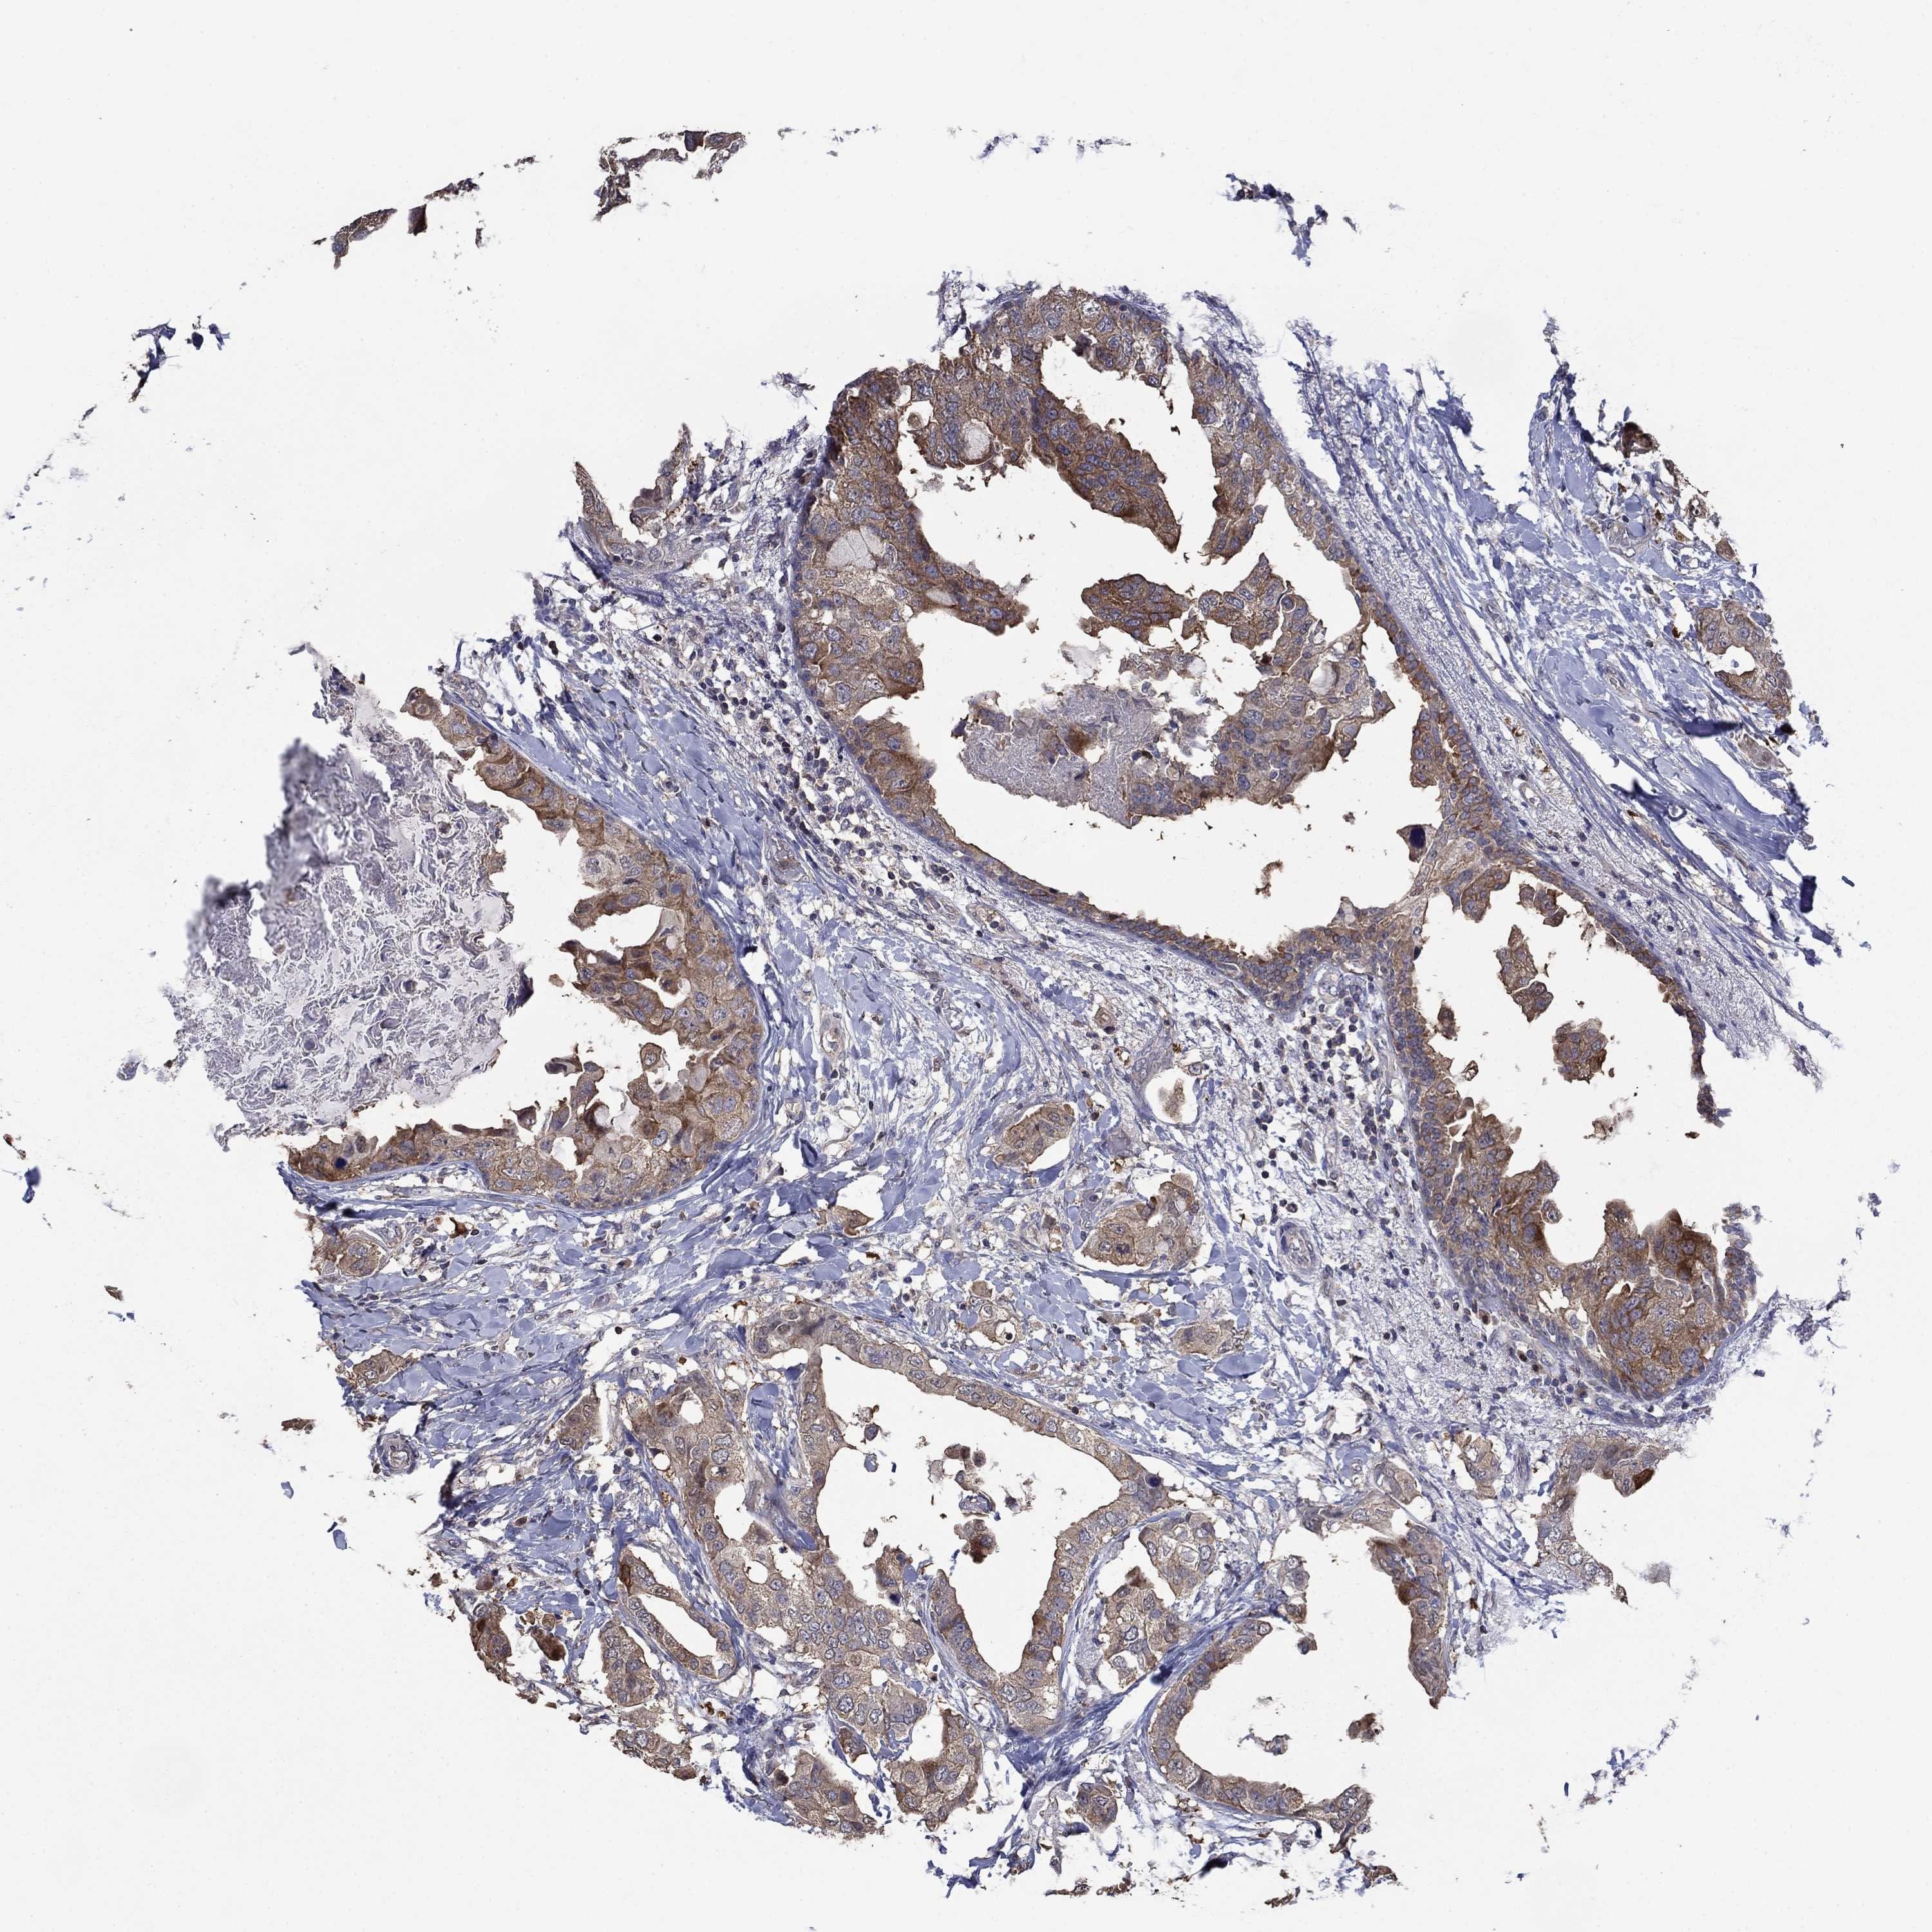

CANCER BREAST CANCER Show tissue menu

BRCA TCGA BRCA VALIDATION PROTEIN EXPRESSION